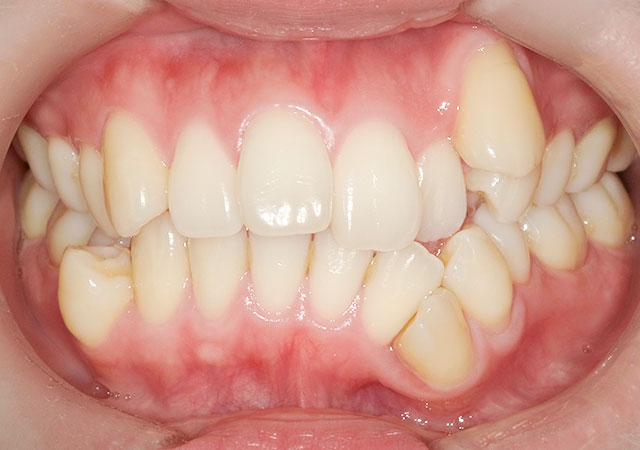

【治療内容】八重歯(叢生)の患者さんです。ワイヤー矯正で歯並びを治しました。

【費用】この方は八重歯の程度がきつかった為に全体矯正で治しました。

ワイヤー矯正 750,000円(税抜)

【リスク】矯正装置が口の中にあたって口内炎が出来やすくなる方もおられます。